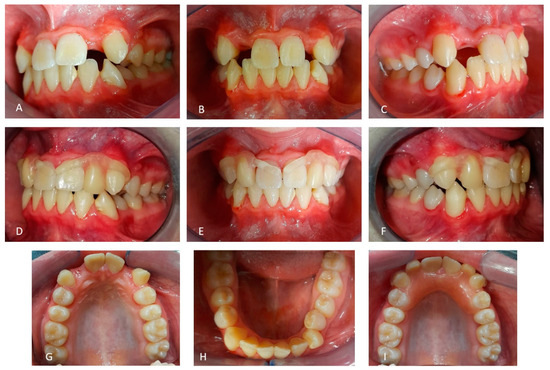

2.1. Patient A

2.2. Patient B

2.3. Father